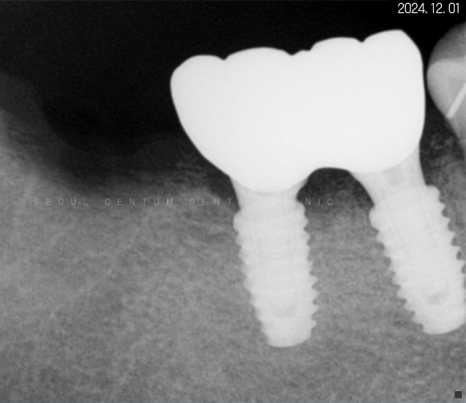

일정 기간이 지난 후 고정력을 체크하고

지대주에 이어서

크라운까지 예쁘게 수복해 드렸습니다~

크라운으로 감싸고 난 후의 치근단 모습입니다.

정확한 간격으로 견고하게 심어졌으며

주변 치조골 양도 풍부합니다.